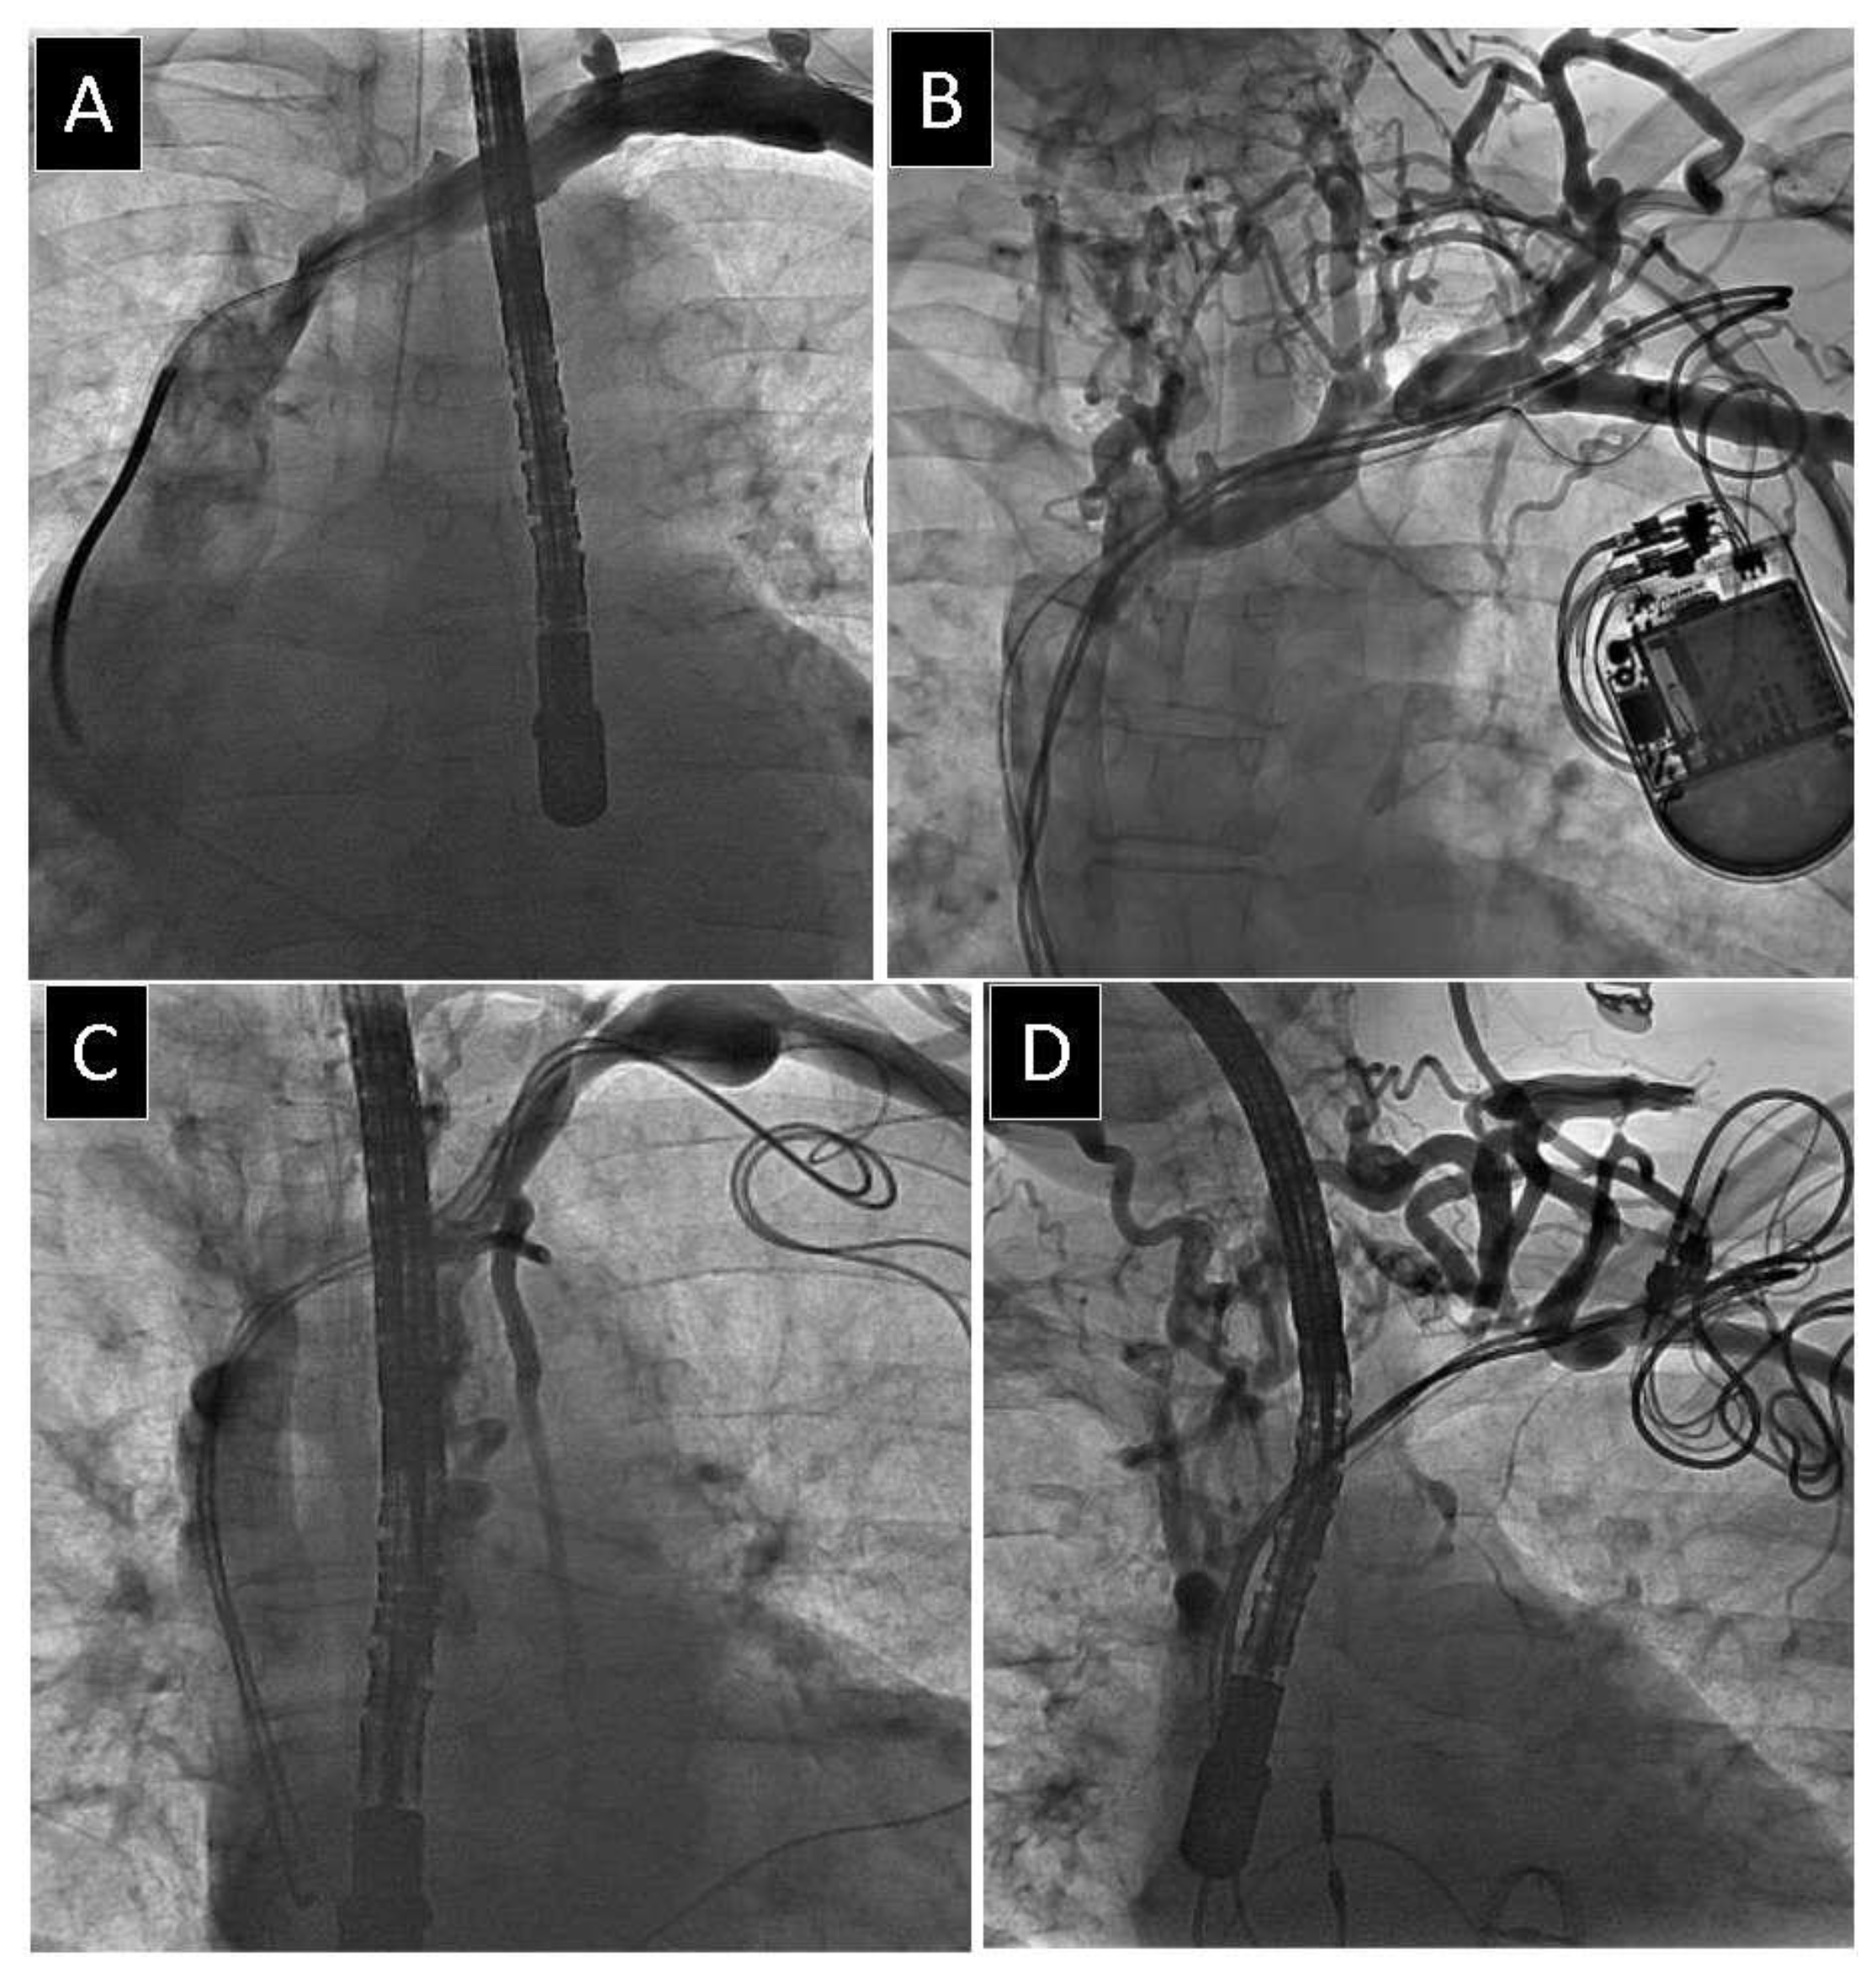

2.2. Venography

2.3. Lead Extraction Procedure